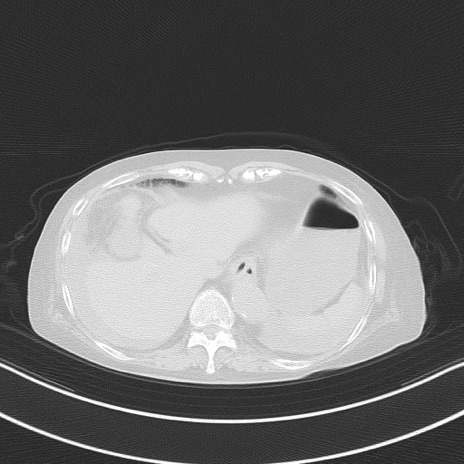

冠状断像